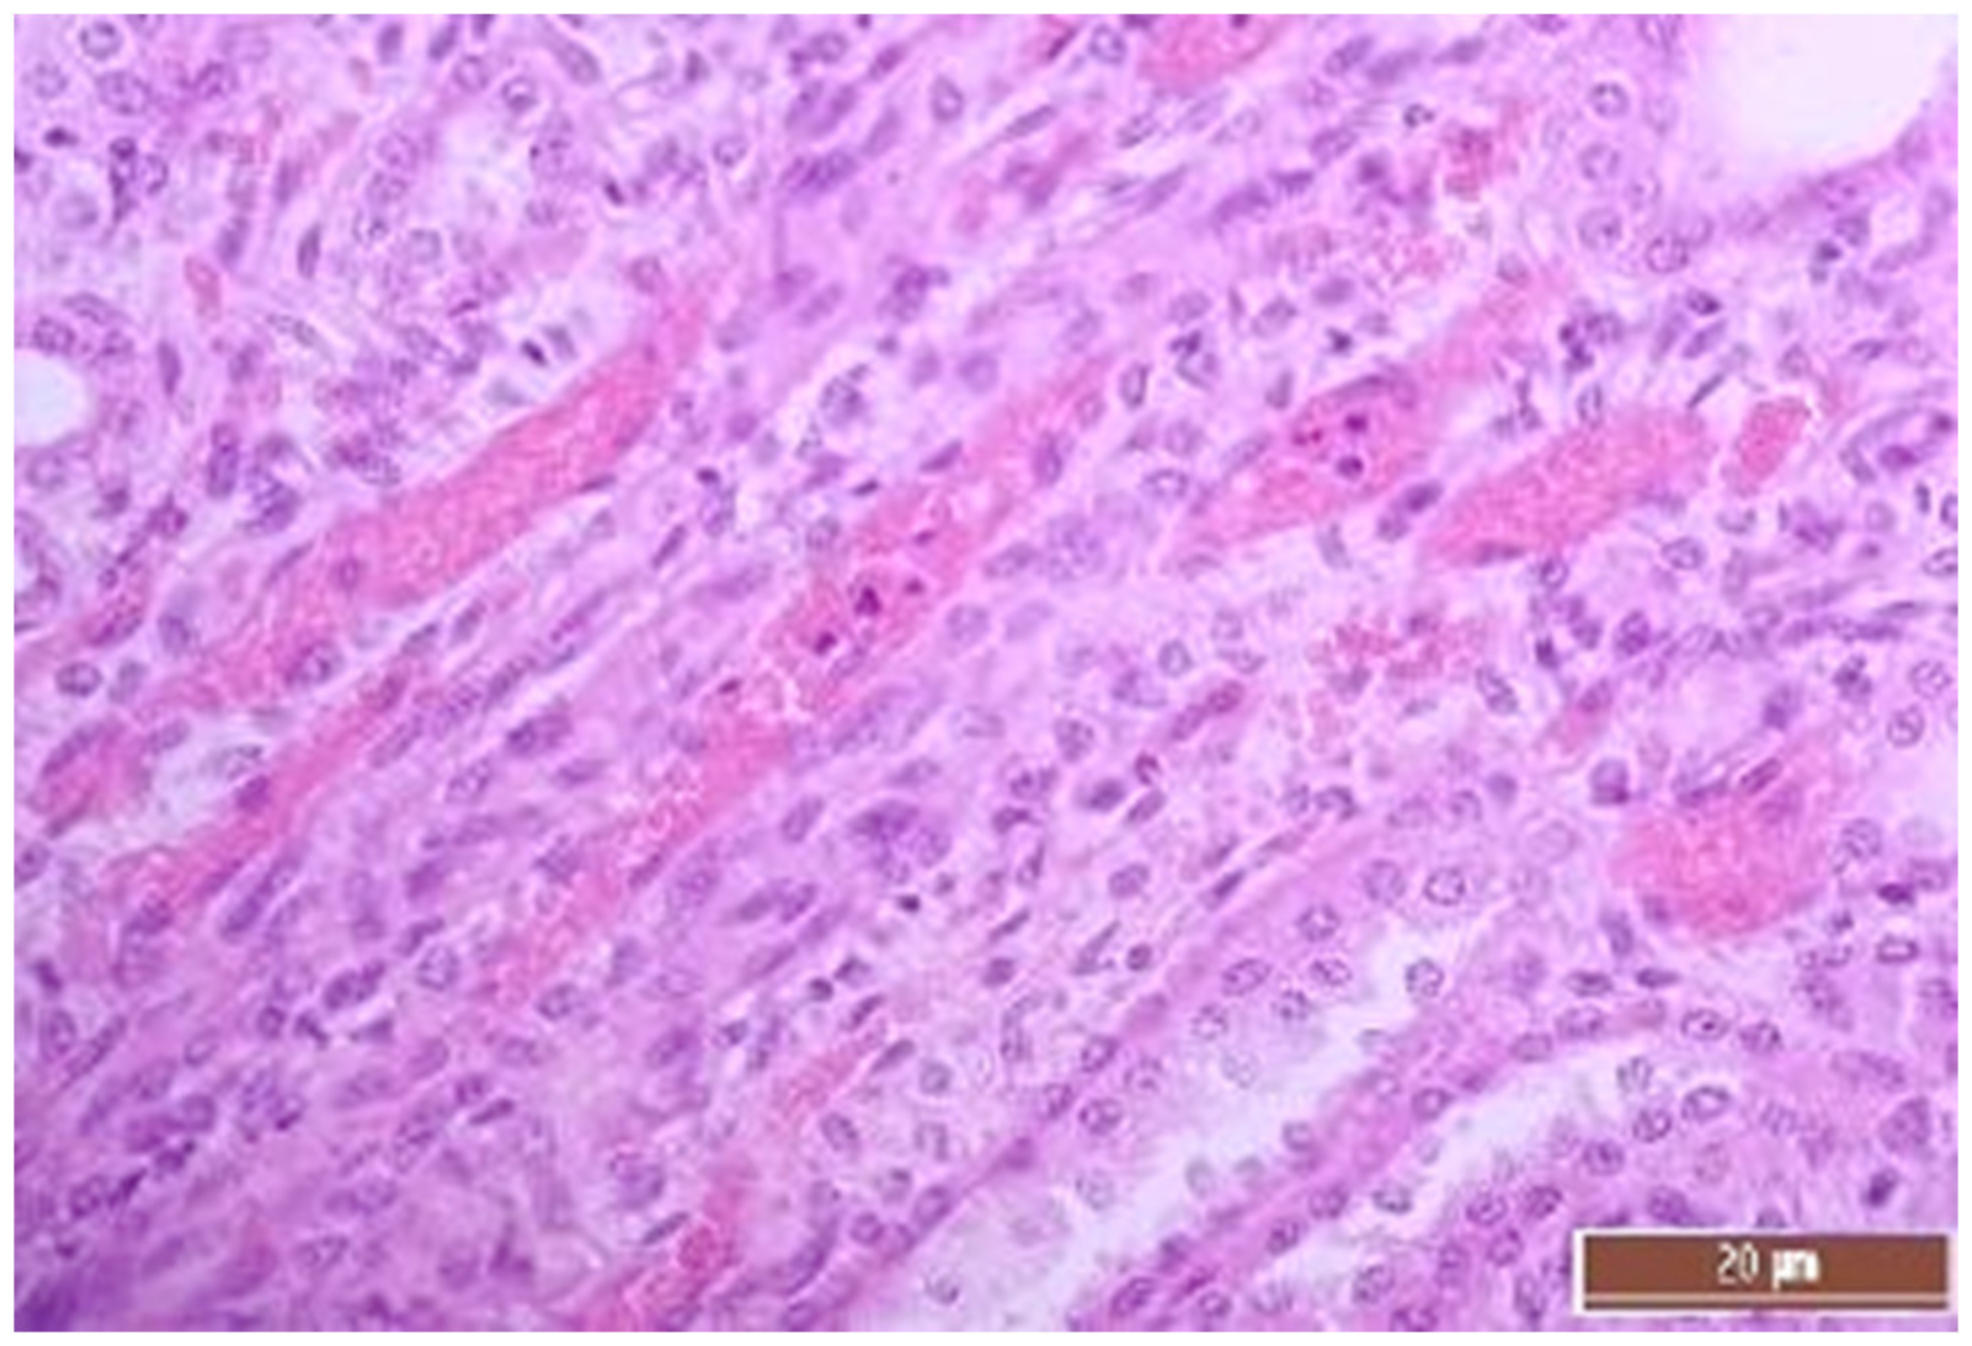

3.2. Pathology of the Liver

3.4. Pathology of Kidneys